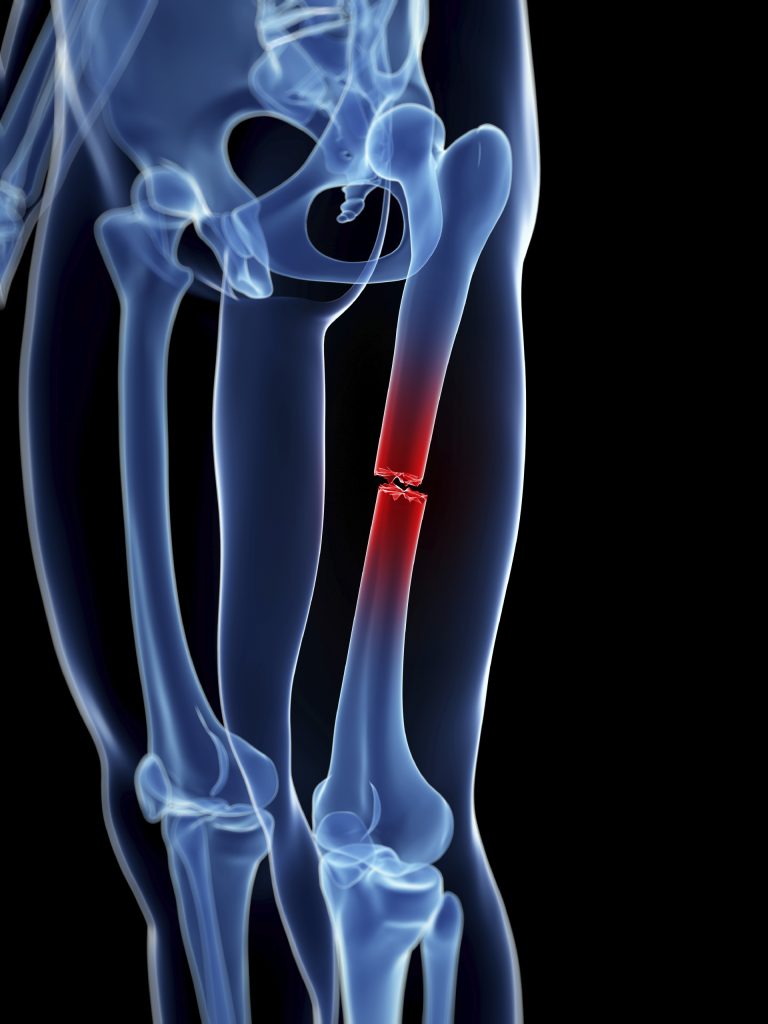

Fractures range from small partial cracks to complete breaks and can occur in any bone.

fracture In more severe cases, the bone may be broken into several fragments, known as a comminuted fracture. Overuse or repetitive motions can cause stress fractures. Fracture d�une porte, d�une serrure. Extends all the way across the bone (most common) transverse fracture: A fracture is a break in the continuity of a bone. An attorney intending on climbing the career ladder toward success finds an unlikely opponent in a manipulative criminal he. Rita riportò due fratture nell�incidente. Fractures usually fall within a set number of patterns.